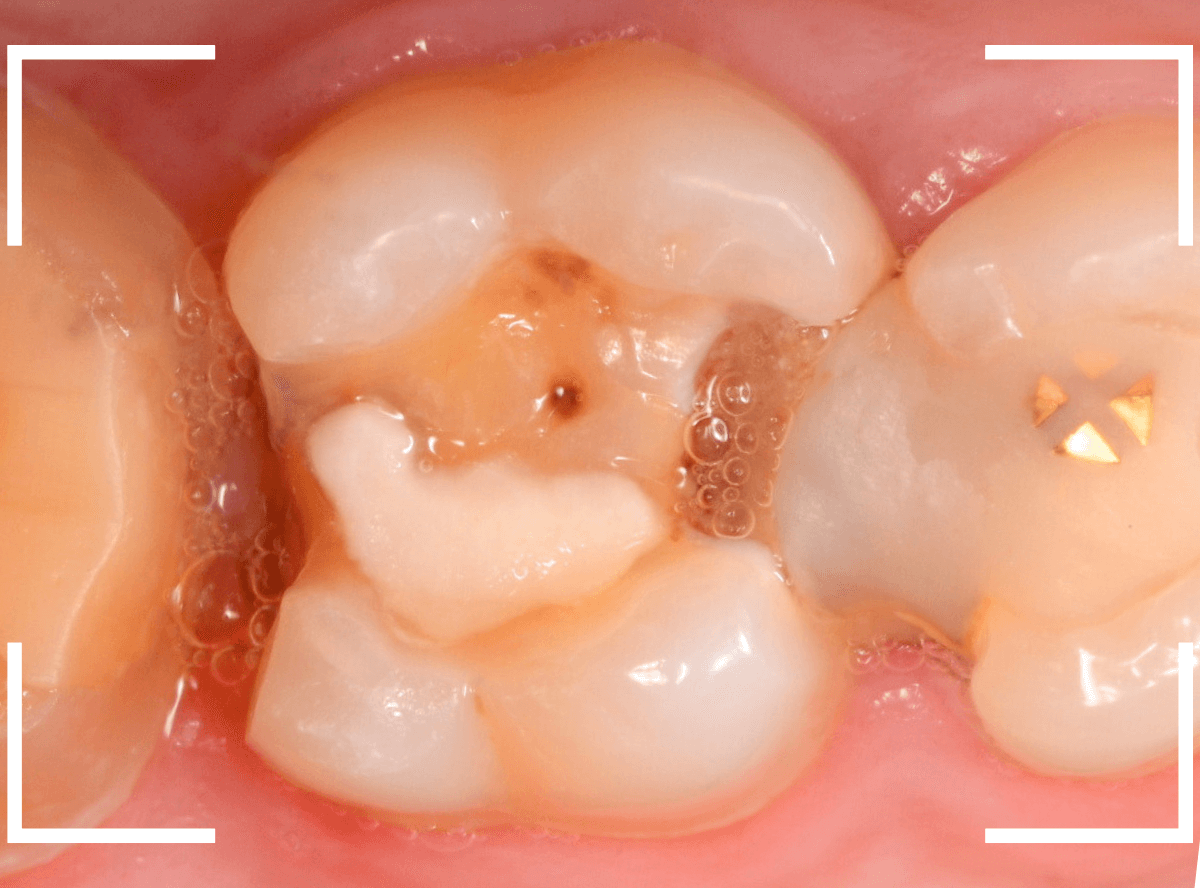

今回は、上のおやしらずが原因で虫歯になってしまった方のケースです。

〇部のおやしらずを虫歯で抜歯しました。

特に問題なさそうに見えますが、「おやしらずを抜歯してから、歯がしみるようになった」との訴えです。

これは、おやしらずを抜歯した後によくある症状です。